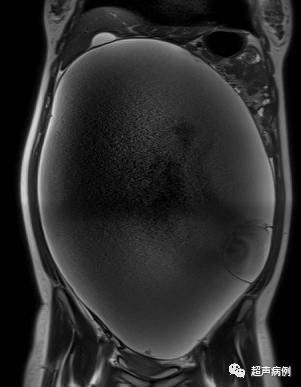

腹盆腔内已出现大小约40.3x29.3x16.0cm的巨大占位性病变。此时,我不由的感叹,常规体检,到底应设置到什么年龄?小学?还是初中?还是。。。

超声检查为一个巨大的囊性占位。

病理诊断为:交界性粘液性囊腺瘤,灶区癌变,高分化粘液腺癌形成。

最后临床诊断:右卵巢高分化粘液性腺癌ⅠA期